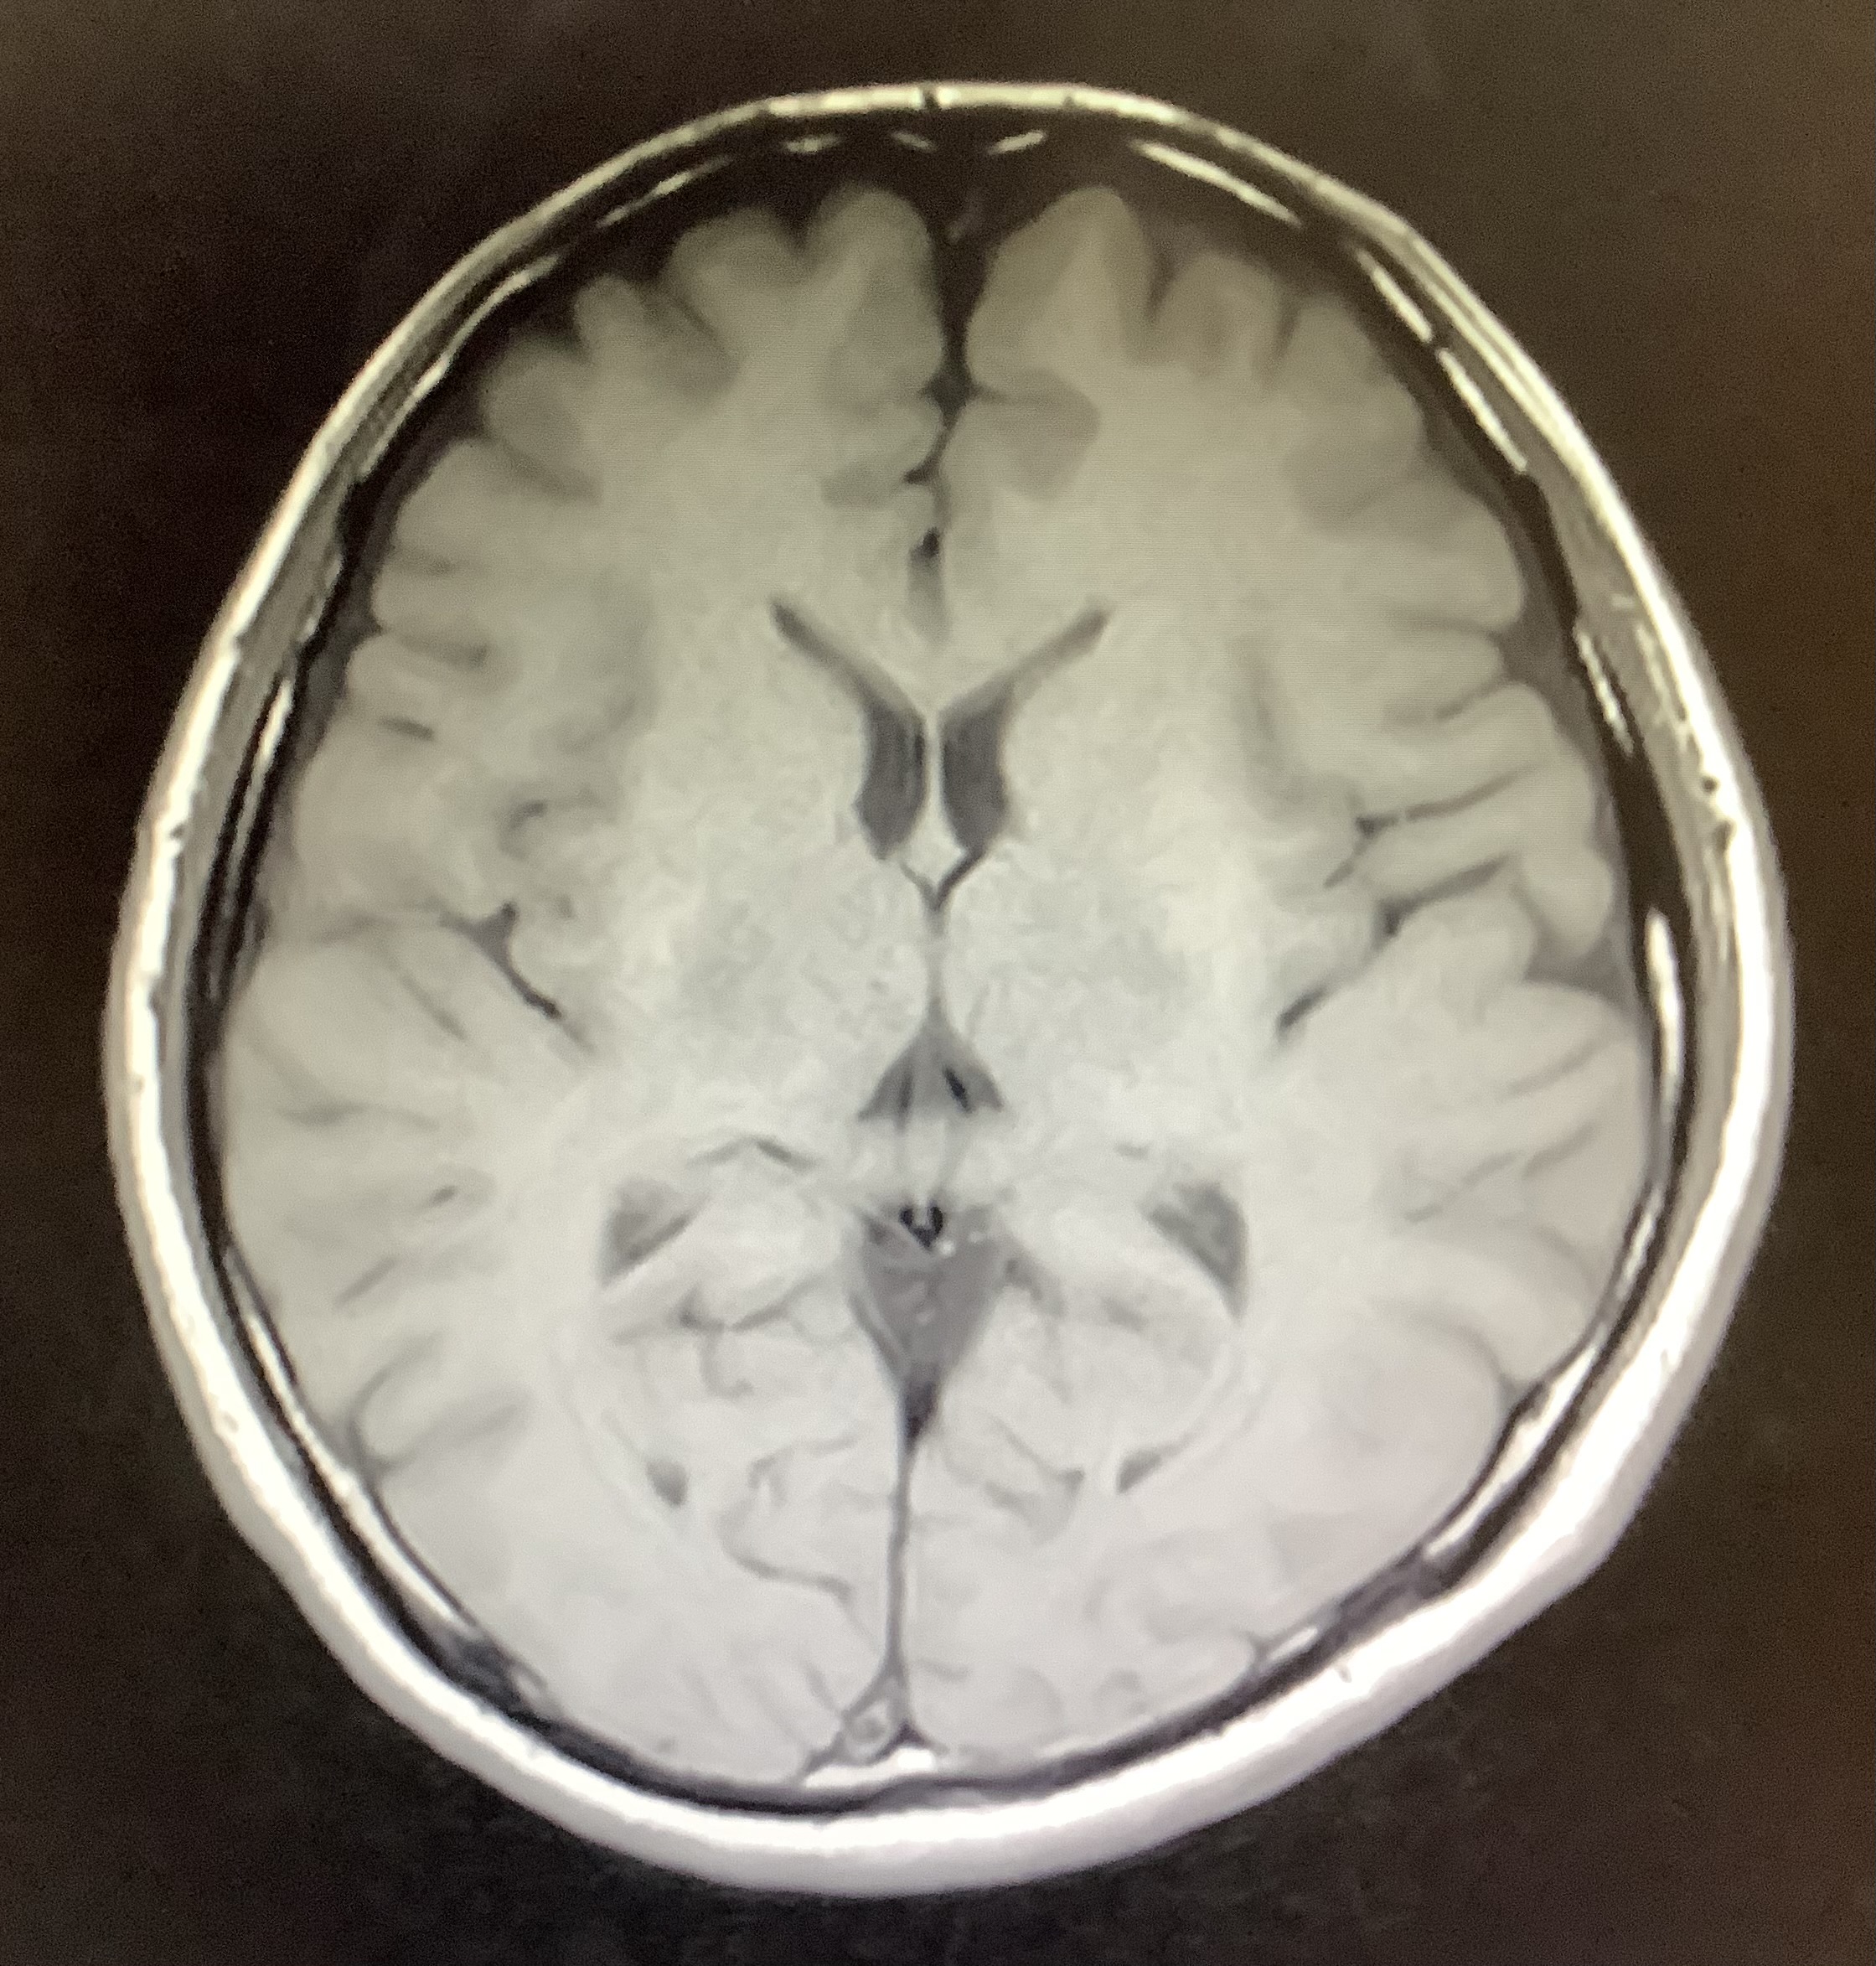

脳ドック

四日市消化器病センターの脳ドックは

頭部MRIと頚部エコーの検査を行っています。頭部MRIでは脳の血管など撮像する事で脳卒中、脳疾患などチェック出来ます。

頚部エコー検査では頚動脈の状態や動脈効果などが分かります。

脳卒中や脳疾患など早期発見や予防に役立ちますので是非

気になる方はご利用ください。